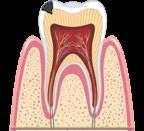

руйнуються під дією органічних кислот, які виділяються численними бактеріями ротової порожнини. Ці бактерії живляться залишками нашої їжі. Карієс виникає через недостатню

гігієну порожнини рота, переважання в раціоні м’якої їжі й вуглеводів. Розвиток карієсу

спричиняє нестача мінералів і вітамінів, які беруть участь у формуванні твердих тканин зубів: Кальцію, Флуору, Фосфору, вітаміну С та інших. До ушкодження емалі зубів також

призводить вживання гарячих, холодних чи

кислих напоїв. Руйнування зуба відбувається

внаслідок бактеріальної інфекції його тканин. X Правила профілактики